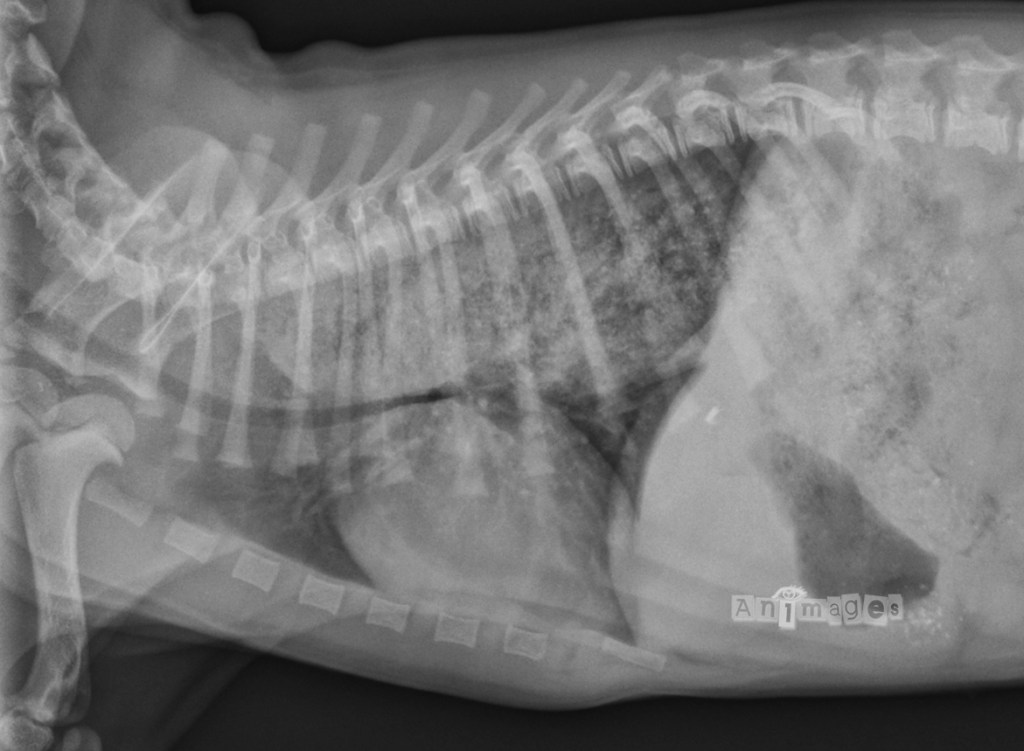

latérale gauche